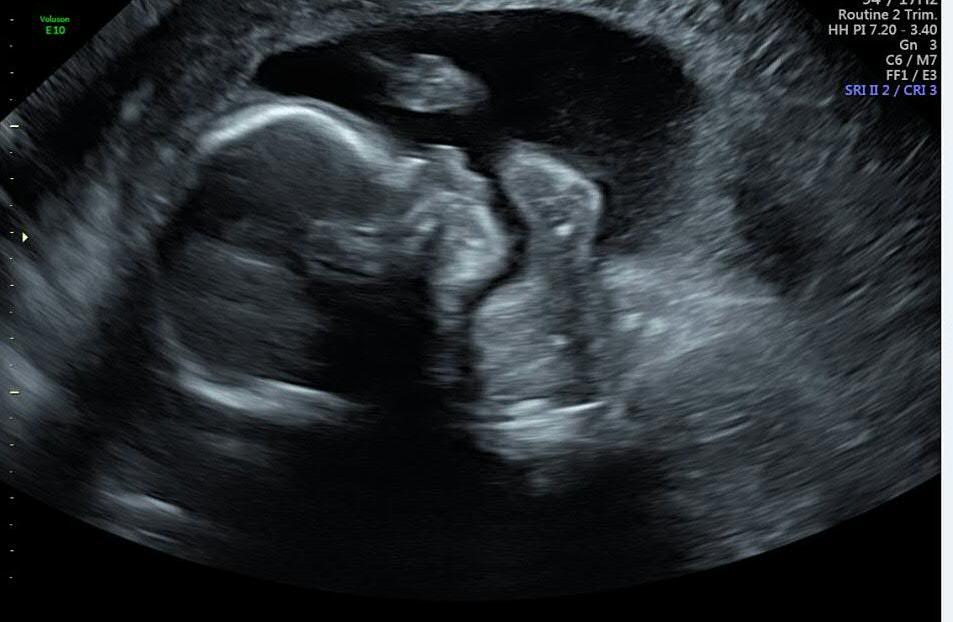

Fotka z utz a pupicek (no, spis pupek) 🙂 zde.